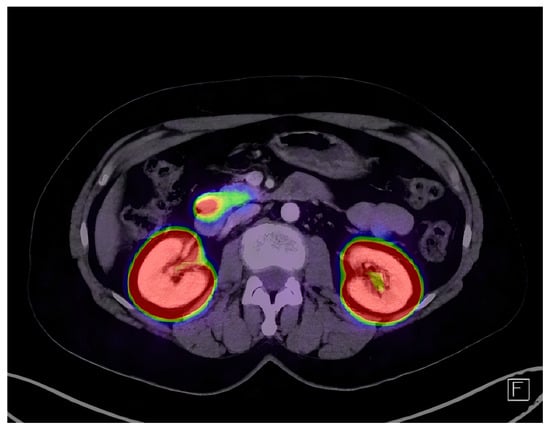

2.3. Imaging and Localization